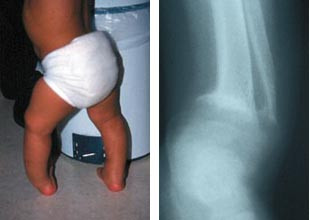

Vitamin D-mangel er også utbredt blant enkelte grupper innvandrerbarn i Norge (28, 29). Det er sannsynlig at vitamin D-status blir dårligere etter migrasjon, selv om det også i de aktuelle gruppenes hjemland er relativt vanlig med vitamin D-mangel (30 – 32). Spesielle risikogrupper ser ut til å være:

– Barn som får langvarig morsmelkernæring

– Maternell vitamin D-mangel

– Kulturelt betinget motstand mot å få sol andre steder enn på hender og i ansikt

– At det ikke gis vitamin D-preparat etter de retningslinjer som helsemyndighetene har satt opp (tilsvarende 10 µg/dag).

Det finnes ingen gode epidemiologiske studier som mer presist dokumenterer forekomsten av rakitt blant barn i Norge. De fleste barn med denne diagnosen vil bli utredet og behandlet av en spesialist i barnesykdommer, som regel i tilknytning til en poliklinisk utredning eller en innleggelse ved en somatisk barneavdeling. Det foreligger ingen innrapportering av barn med rakitt til noe sentralt register. For å få en oversikt over problemets omfang sendte vi et spørreskjema til alle landets barneavdelinger i januar 2000, der vi spurte etter hvor mange tilfeller med rakitt som var behandlet ved den aktuelle enhet i løpet av 1998 og 1999. 25 av 30 barneavdelinger svarte. Disse dekker> 95 % av den norske barnepopulasjonen. 65 barn med ernæringsbetinget rakitt ble registrert. 54 av barna hadde innvandrerbakgrunn (begge foreldre født i utlandet). 20 barn hadde bakgrunn fra Pakistan. 18 av disse barna kom fra Oslo, og det representerer ca. 50 % av barna som ble behandlet for rakitt i Oslo i perioden. Øvrige nasjoner som var representert var Marokko, Irak, Iran, Tyrkia, Bosnia, Madagaskar, Somalia, Kosovo, Sri Lanka, Albania, Korea og Libanon. Foreldrenes trosoppfatning ble ikke registrert. 23 barn var under ett år, 28 barn mellom ett og to år og 14 barn mer enn to år. Tallene tyder på at alimentær rakitt ikke er uvanlig i Norge, og at det er behov for å bedre det forebyggende arbeidet på dette området.